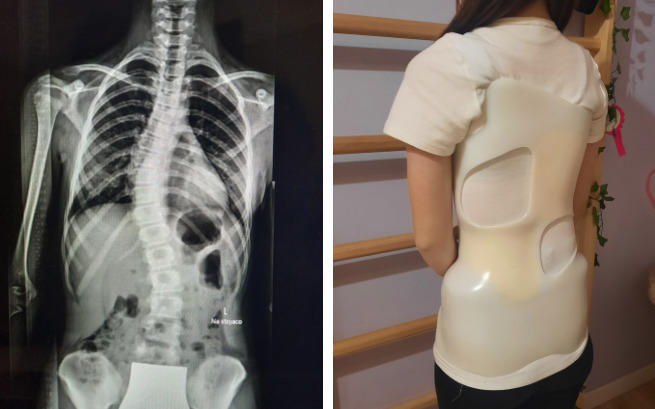

Blanka skarżyła się już na bóle pleców. Ale chodziła do szkoły z ciężkim plecakiem, ćwiczyła… Po bilansie w szkole została skierowana do pediatry z podejrzeniem wady postawy, a stamtąd do ortopedy.

Ten stwierdził skoliozę dwułukową. Prawostronna na 35 stopni w odcinku piersiowym i lewostronna 25 stopni w odcinku lędźwiowym. Zlecił nam konieczne kompleksowe leczenie zachowawcze – ćwiczenia antyskoliotyczne asymetryczne i specjalny gorset.

Dla Blanki stało się to chyba w najgorszym możliwym momencie. W wakacje znalazła swoją nową pasję, jazdę konną, z której przez skoliozę musiała zrezygnować na kto wie ile? Czasem też wracają bóle, ponieważ ciało musi przystosować się do gorsetu.